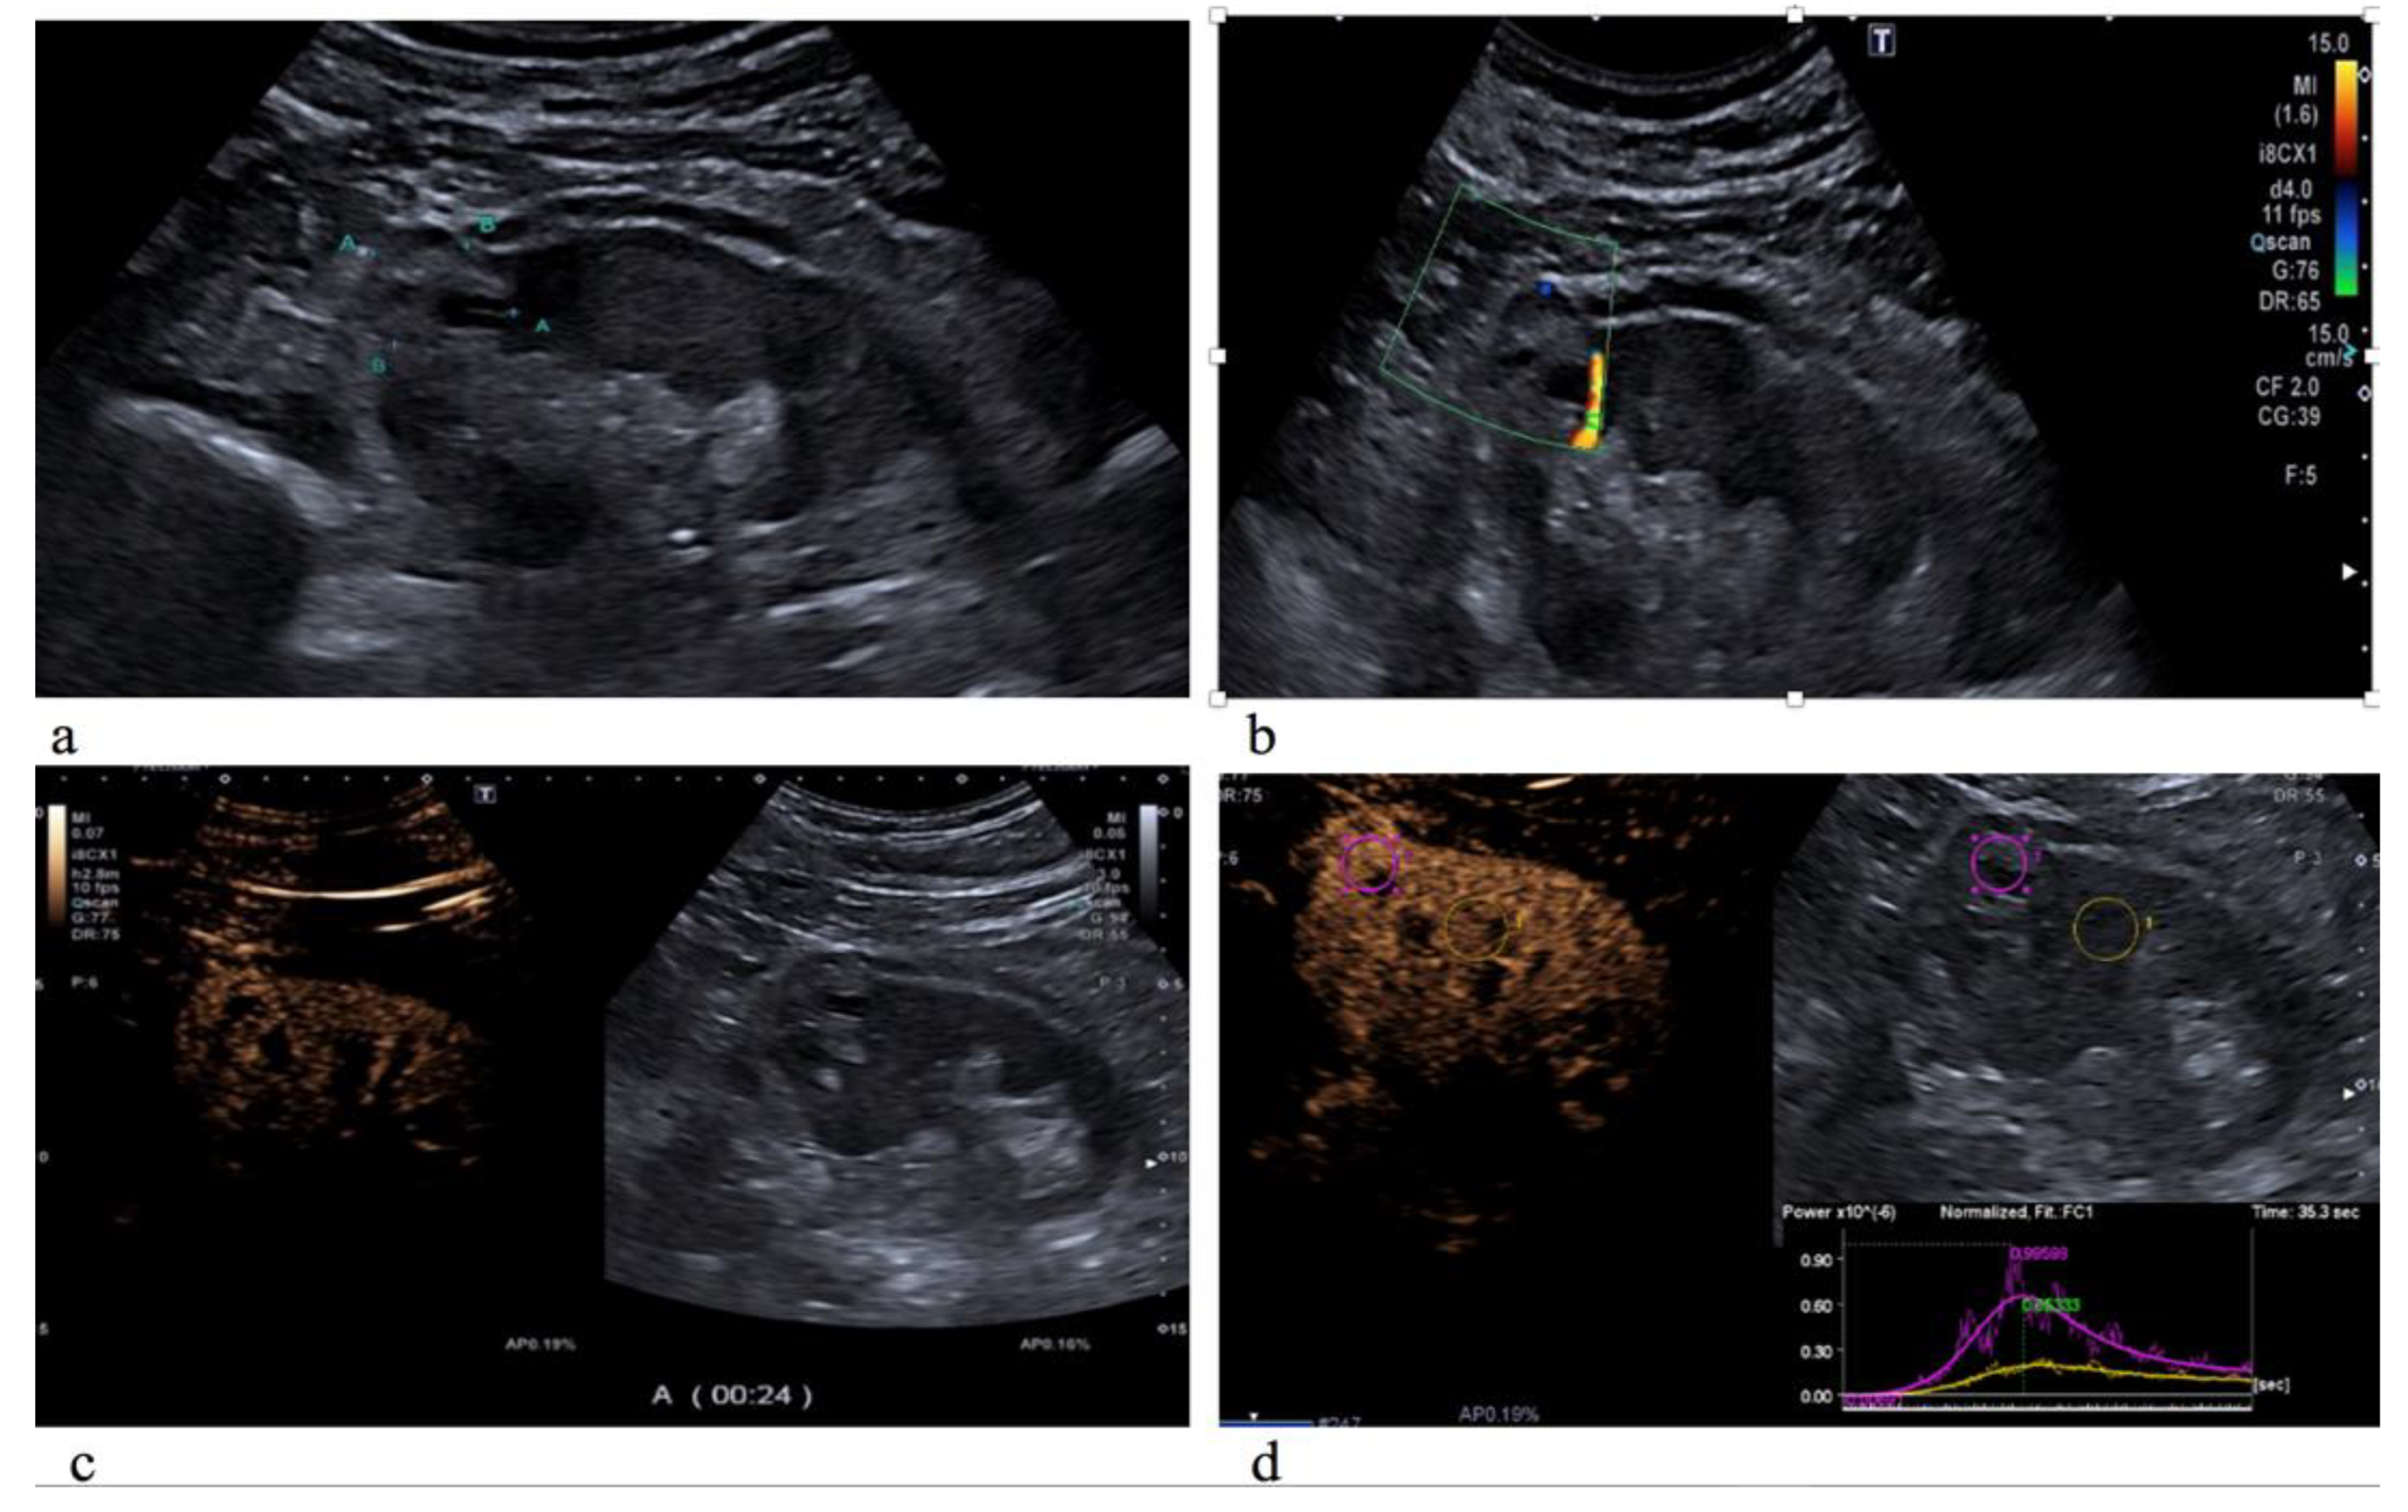

Overall, 110 patients (8 presenting with multiple masses) with a total of 118 lesions were evaluated by US B-mode, CDI and CEUS. Of those, 88 (75%) were malignant and 30 (25%) were benign. Patients and tumor characteristics are described in Table 1. All patients underwent NSS. Median age was 63 years (IQ: 55–71) and the median tumor size was 2.85 cm (range: 1.5–3.9 cm) with a median R.E.N.A.L. score of 7 (IQ: 6–9). Histologically, 88 lesions were classified as malignant (72 clear cell renal cell carcinoma (Figure 1), 6 type I papillary renal cell carcinoma, 4 clear cell cystic carcinoma, 4 clear cell multicystic carcinoma and 2 chromophobe renal cell carcinoma) and 30 as benign lesions (16 oncocytoma, 10 angiomyolipoma, 2 renal abscess and 2 hemorrhagic cyst) (Table 2).

Figure 1.

Clear cell carcinoma on the upper pole of the left kidney, characterized by an inhomogeneous hyperechoic echotexture with fluid-filled lacuna (a); on color Doppler US evaluation, it appeared with poor peripheral vascularization (b); and on CEUS evaluation, the lesion showed rapid and inhomogeneous enhancement compared to the normal renal cortex parenchyma (c). As showed by the time-intensity curve (d), the renal mass has a higher peak of the signal intensity (PI) and an incremented regional blood volume (RBV) in comparison to the surrounding healthy parenchyma.